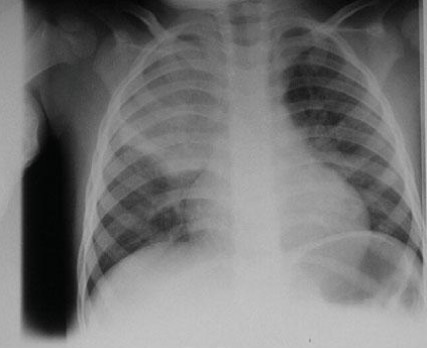

Common X-ray Findings: